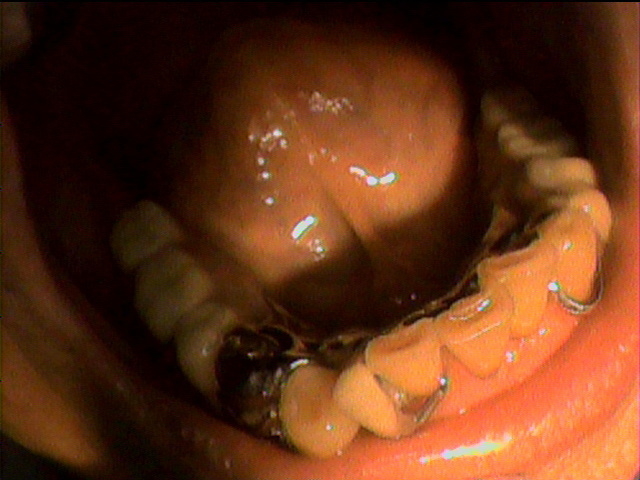

本日、出来上がりました自費の部分入れ歯ー下顎メタルプレートの症例です。

81歳の女性OUさんはとけも若々しいかたで、上下ともに、ぶぶん入れ歯ですが、今回は下顎の左右の奥歯のメタルプレートの入れ歯を新しく作りました。

自費によるメタルプレート義歯で、薄く丈夫な義歯として、とても舌感の良好な状態にすることができ、さらに自由な義歯の設計ができるため、残っているはにかける針金は白金加金で作成し、残存歯にやさしい設計となっており、舌に触れるバー部分はコバルトクロム合金で、丈夫に薄く作ってあります。

(参考代金;30万円)